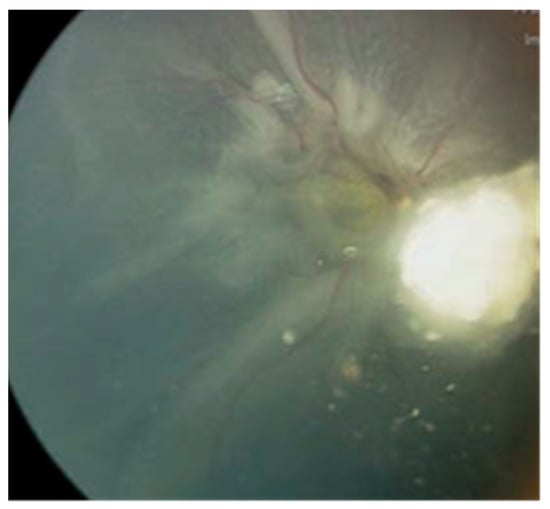

Case #3: A 2-year-old male, diagnosed with bilateral Rb, had already undergone enucleation for the left eye in a different country. Before being referred to our center, he received six cycles of systemic chemotherapy to manage the active tumors in the right eye. Upon the first assessment at our center, the right eye exhibited active Rb, subtotal RRD, and a tractional component (Figure 2).

An effort was made to address the retinal detachment using a conventional approach involving scleral buckling and retinopexy without fluid drainage. While there was a minor improvement in the retinal detachment after the surgical procedure, the tumor displayed resistance to chemotherapy and continued to enlarge. The retina failed to reattach over a three-month postoperative follow-up period, and the tumor persisted in its growth. Due to the poor prognosis for vision and the heightened risk of metastasis, the decision was ultimately made to proceed with enucleation of the right eye.

Figure 2. (Case #3) Fundus photo for the right eye shows active Rb with subtotal RRD and a tractional component.